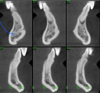

3 types of md ridge morphology

line A represents line of reference - 2mm coronal to IAN